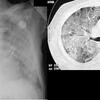

加湿器肺(Humidifier Lung, HL)は、過敏性肺炎(Hypersensitivity Pneumonitis, HP)の一種とされる疾患で、肺にアレルギー反応を引き起こします。この症状の原因は何なのでしょうか?

Clinical and radiological characteristics of ultrasonic humidifier lung and summer-type hypersensitivity pneumonitis. Respir Med. 2020;174:106196.